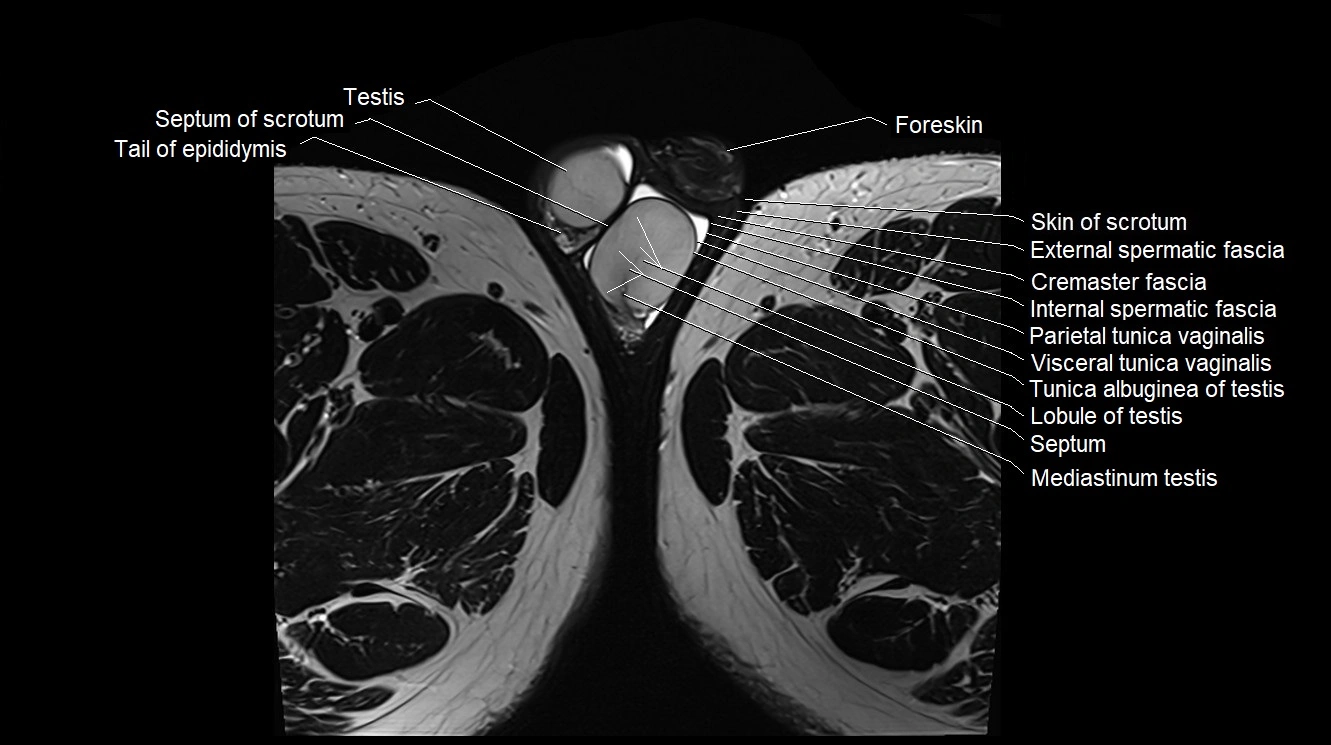

MRI image